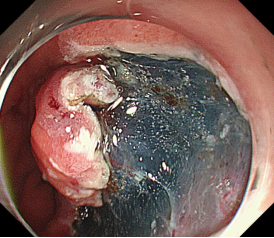

消化道早癌的病例展示(经内镜手术或活检证实):

胃角的腺癌

胃窦的腺癌 行ESD治疗

术中见较粗穿支血管,裸化后凝除,最终高效、安全的切除病灶。